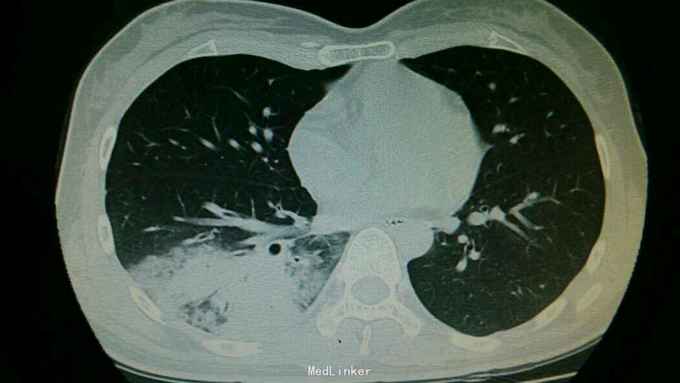

主诉:发热伴咳嗽1周 病史:患者1周前无明显诱因出现发热,最好体温40度,伴有头痛,畏寒咳嗽。

查体:右下肺可闻及湿性啰音。余无特殊。 辅查:右肺下叶大叶性肺炎。

诊断:大叶性肺炎。 治疗:入院予以抗感染,止咳化痰等治疗。

随访+讨论:大叶性肺炎常见于肺炎链球菌感染,主要治疗予以抗感染治疗。还患者予以抗感染治疗后病情好转。